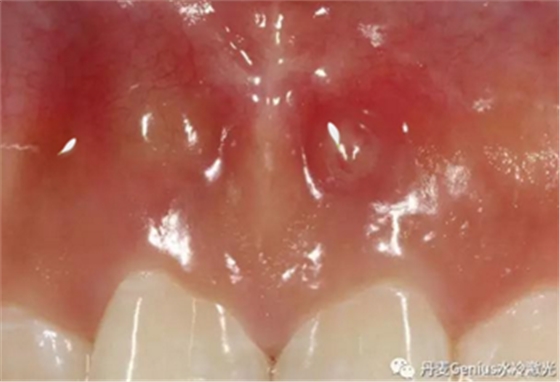

淺表黏膜膿腫切開(kāi)引流

在常規(guī)消毒后,涂抹本品,再行切割。在更換藥物時(shí),也可以涂抹